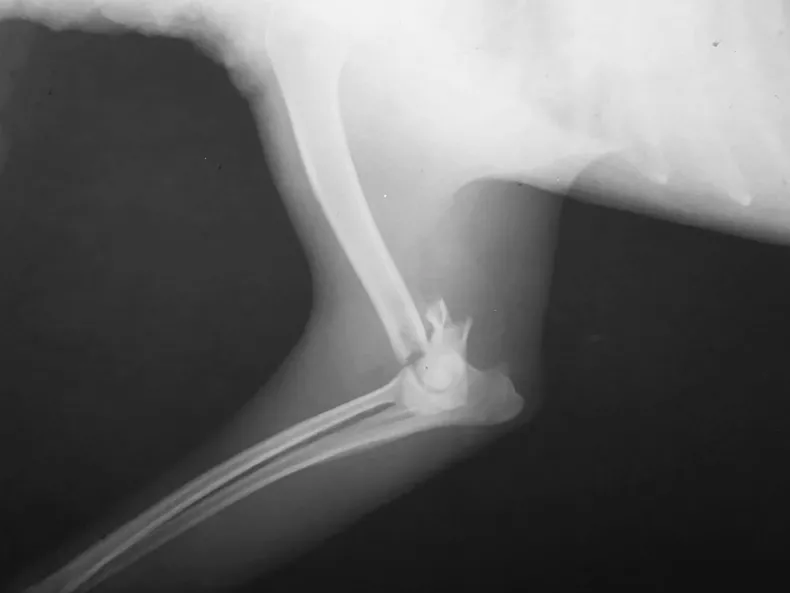

Según relataron desde Fundación Castraciones Chaco, el animal fue encontrado en estado de sufrimiento y sin recibir ningún tipo de asistencia. Tras ser trasladado a una clínica veterinaria, se constató que presenta una fractura distal de húmero izquierdo con compromiso de los epicóndilos lateral y medial, por lo que necesita una cirugía urgente.

El procedimiento incluye estudios radiográficos, medicación, intervención quirúrgica con colocación de placa y tornillos, y tratamiento postoperatorio.El costo total de la atención y la cirugía asciende a 418 mil pesos, un monto que la fundación no puede afrontar por sus propios medios.